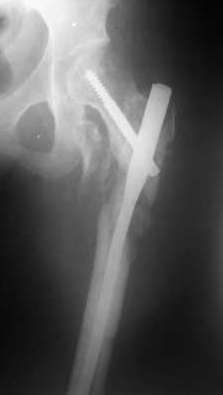

Девушка 21 года 02.10.07 г. пострадала в результате падения с высоты 4-го этажа при пожаре в одном из студенческих общежитий г. Москвы. Получила тяжелую сочетанную травму, в том числе закрытый оскольчатый чрез- и подвертельный перелом левой бедренной кости. Лечилась в одной из больниц столицы. Бедро было фиксировано при помощи скелетного вытяжения. Через полтора месяца после травмы переведена в институт им. Склифосовского. У больной имелись: поддиафрагмальный абсцесс, трахеопищеводный свищ, трахеостома, гастростома, несостоятельность швов раны передней брюшной стенки, укорочение левого бедра на 10 см (рентгенограммы при поступлении - рис 1.). В середине декабря был наложен спицестержневой аппарат, с помощью которого к сегодняшнему удалось устранить укорочение бедра (рис. 2). В течение последних 4-х дней устраняем смещение дистального отломка бедренной кости по ширине. Раны на передней брюшной стенке почти зажили. Температура тела и лабораторные показатели нормальные. Планируем выполнить закрытый остеосинтез левой бедренной кости удлиненным проксимальным бедренным штифтом производства фирмы "Остеомед". Нас смущает, что малый вертел бедренной кости остается значительно смещенным проксимально и кнутри.